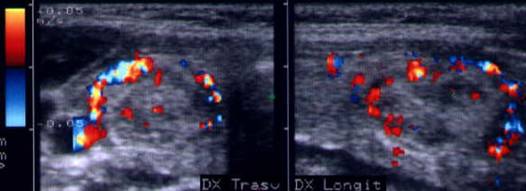

Femeie 26 ani. Nodul mare de consistenta crescuta de 14 cc, care ocupa quasi complet lobul drept; contur net, neomogen, micro si macrocalcificari. Citoaspiratie – nodul hiperplazic

Aceeasi pacienta.Vascolarizatie periferica si

intranodulara.